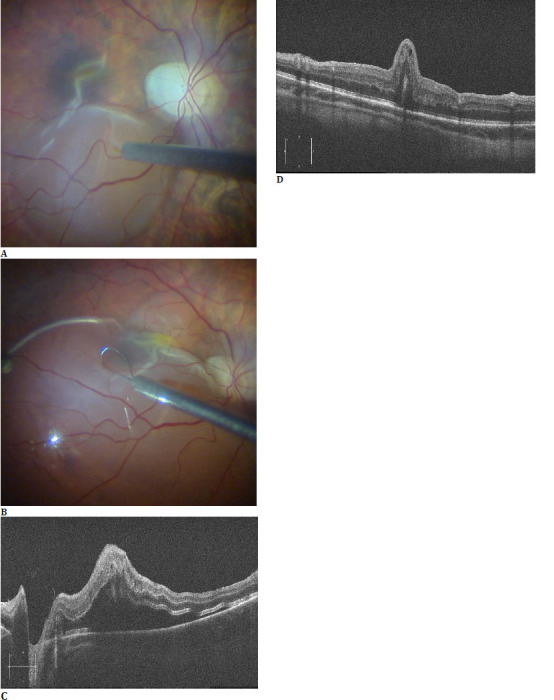

Results: A 22-year-old man with a stage 3 ERM, visual acuity (VA) of 20/100, and a history of scleral buckle underwent pars plana vitrectomy (PPV) with internal limiting membrane (ILM) peeling. One week after surgery, VA dropped to 20/125 with worsened metamorphopsia. Ophthalmoscopy revealed a fovea-involving full-thickness macular fold, with photoreceptor outer segments in opposition. After 3 weeks of follow-up without improvement, PPV with induction of localized retinal detachment was performed, combined with retinal massage. Moreover, perfluorocarbon liquid (PFCL) was employed to stretch the retina. Nevertheless, the macular fold and metamorphopsia were unchanged, even one year after the first surgery.

Discussion: We hypothesize that, due to the highly contracted ERM, the retina may have separated from the RPE during peeling and folded over in the first postoperative days. Concurrently, incorrect patient positioning under air tamponade might have contributed to the vertical orientation of the fold.